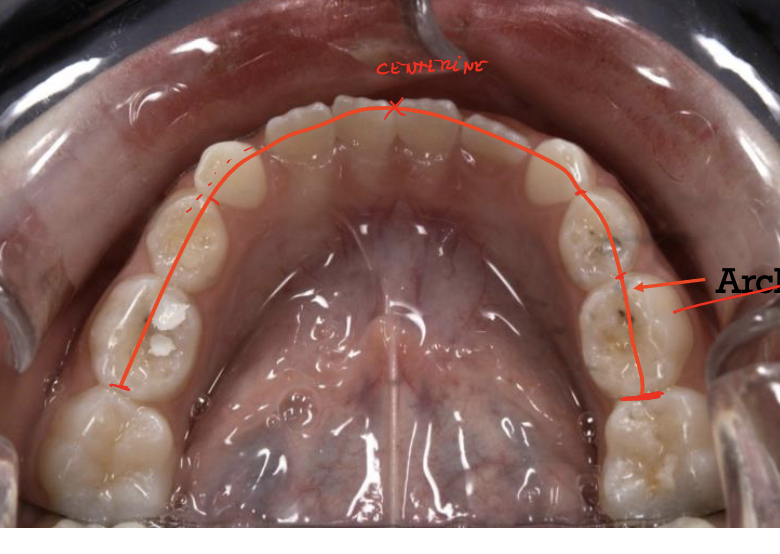

Dental Arch measurements

A

length

width

perimeter

intercanine distance

Arch length (depth)

becomes stable when?

displacement?

Measured at the midline to a tangent touching the distal surfaces of the second primary molars

arch length is stable once the incisors erupt

displaced in space with growth

Arch width

• Measured between the cups of the canines in the transverse plane

• Measured between the occlusal grooves of the second primary molars or the upper/lower permanent first molars

Arch perimeter

Measured from the distal surface of the second primary molar (or mesial of the permanent first) around the arch over the contact points and incisal edges in a smoothed curve